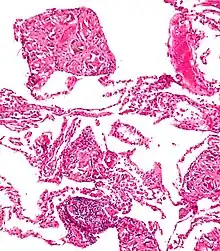

Skin

Surgical suture. H&E stain.

Splinters are common foreign bodies in skin. Staphylococcus aureus infection often causes boils to form around them.[11]

Tetanus prophylaxis may be appropriate.[12]